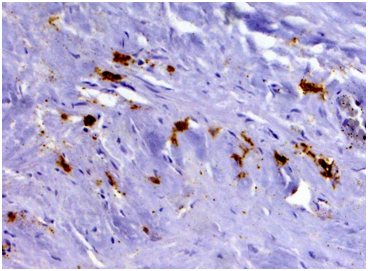

Biopsy of retroperitoneal mass: pathology evaluation (Figures 2‒4) by light microscopy sections of formalin fixed paraffin embedded tissue, stained with periodic acid-Schiff and Haematoxylin-Eosin, represented mostly coarse fibrous tissue with prominent desmoplastic changes, and focal lymphoid infiltration with substantial admixture of plasma cells. Fine focal lymphocyte and plasma cell aggregates were found also per vascular in the depth of fibrous tissue. Immunohistochemistry on formalin fixed paraffin embedded tissue with immuno peroxidase staining for IgG4, CD138, CD3 and CD20 showed diffuse (80%) prominent expression of CD20+, diffuse multifocal (40%) prominent expression of CD138+, and focal (<20%) moderate expression of CD3+. Vast majority of CD138 positive cells showed also diffuse moderate expression of IgG4 (up to 15-20 IgG4 positive plasma cells per field with magnification x400).

Figure 4 Immunohistochemistry showing seven IgG4-positive plasma cells per hpf (Immunoperoxidase, х 400.).